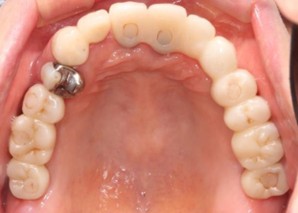

20代 男性

治療前

治療後

治療後- リスク・副作用

(薬・注射・レントゲン・CT・データ分析・骨造成・サージカルステント・血液検査・仮歯) - 年齢/性別

- 20代/男性

- 患者の具体的な症状

- 1年前に左上12 右上1の根の治療をし、その後放置していたら、左上2が破折した。

左上2インプラント補綴 左上1右上1オールセラミック装着。

歯根破折と虫歯による痛み、審美障害を主訴として来院。 - 検査方法

- コーンビームCT、レントゲン撮影

- 診断結果

- 左上2 歯根破折

- 治療詳細

- 左上抜歯後、インプラント埋入1本

骨造成あり 局所麻酔

インプラント治療後、左上1右上1セラミック修復2本 - 通院回数

- 9回

- 治療期間

- 12か月